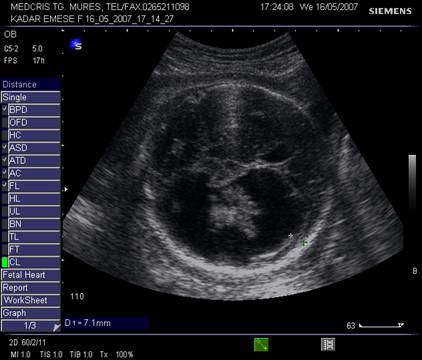

Fig. nr. 249. Hidrocefalie interna unilaterala aparuta la 28 sapt si cu evolutie rapida, postpartum se confirma suspiciunea de diagnostic: hemoragie cerebrala